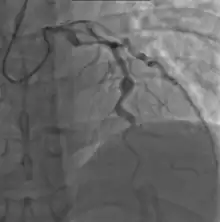

Heart complications are the most important aspect of Kawasaki disease, which is the leading cause of heart disease acquired in childhood in the United States and Japan.[31] In developed nations, it appears to have replaced acute rheumatic fever as the most common cause of acquired heart disease in children.[15] Coronary artery aneurysms occur as a sequela of the vasculitis in 20–25% of untreated children.[52] It is first detected at a mean of 10 days of illness and the peak frequency of coronary artery dilation or aneurysms occurs within four weeks of onset.[48] Aneurysms are classified into small (internal diameter of vessel wall <5 mm), medium (diameter ranging from 5–8 mm), and giant (diameter > 8 mm).[31] Saccular and fusiform aneurysms usually develop between 18 and 25 days after the onset of illness.[15]

- Angiography was historically used to detect coronary artery aneurysms, and remains the gold standard for their detection, but is rarely used today unless coronary artery aneurysms have already been detected by echocardiography.